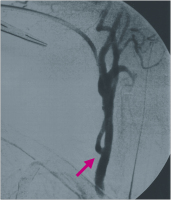

Angiographie

Abbildung 2: Postoperative Angiographie: Bypass (roter Pfeil) von der linken Art. subclavia (peripher des Abgangs der Art. vertebralis, grüner Pfeil) auf die rechte Art. carotis communis (grüner Pfeil).